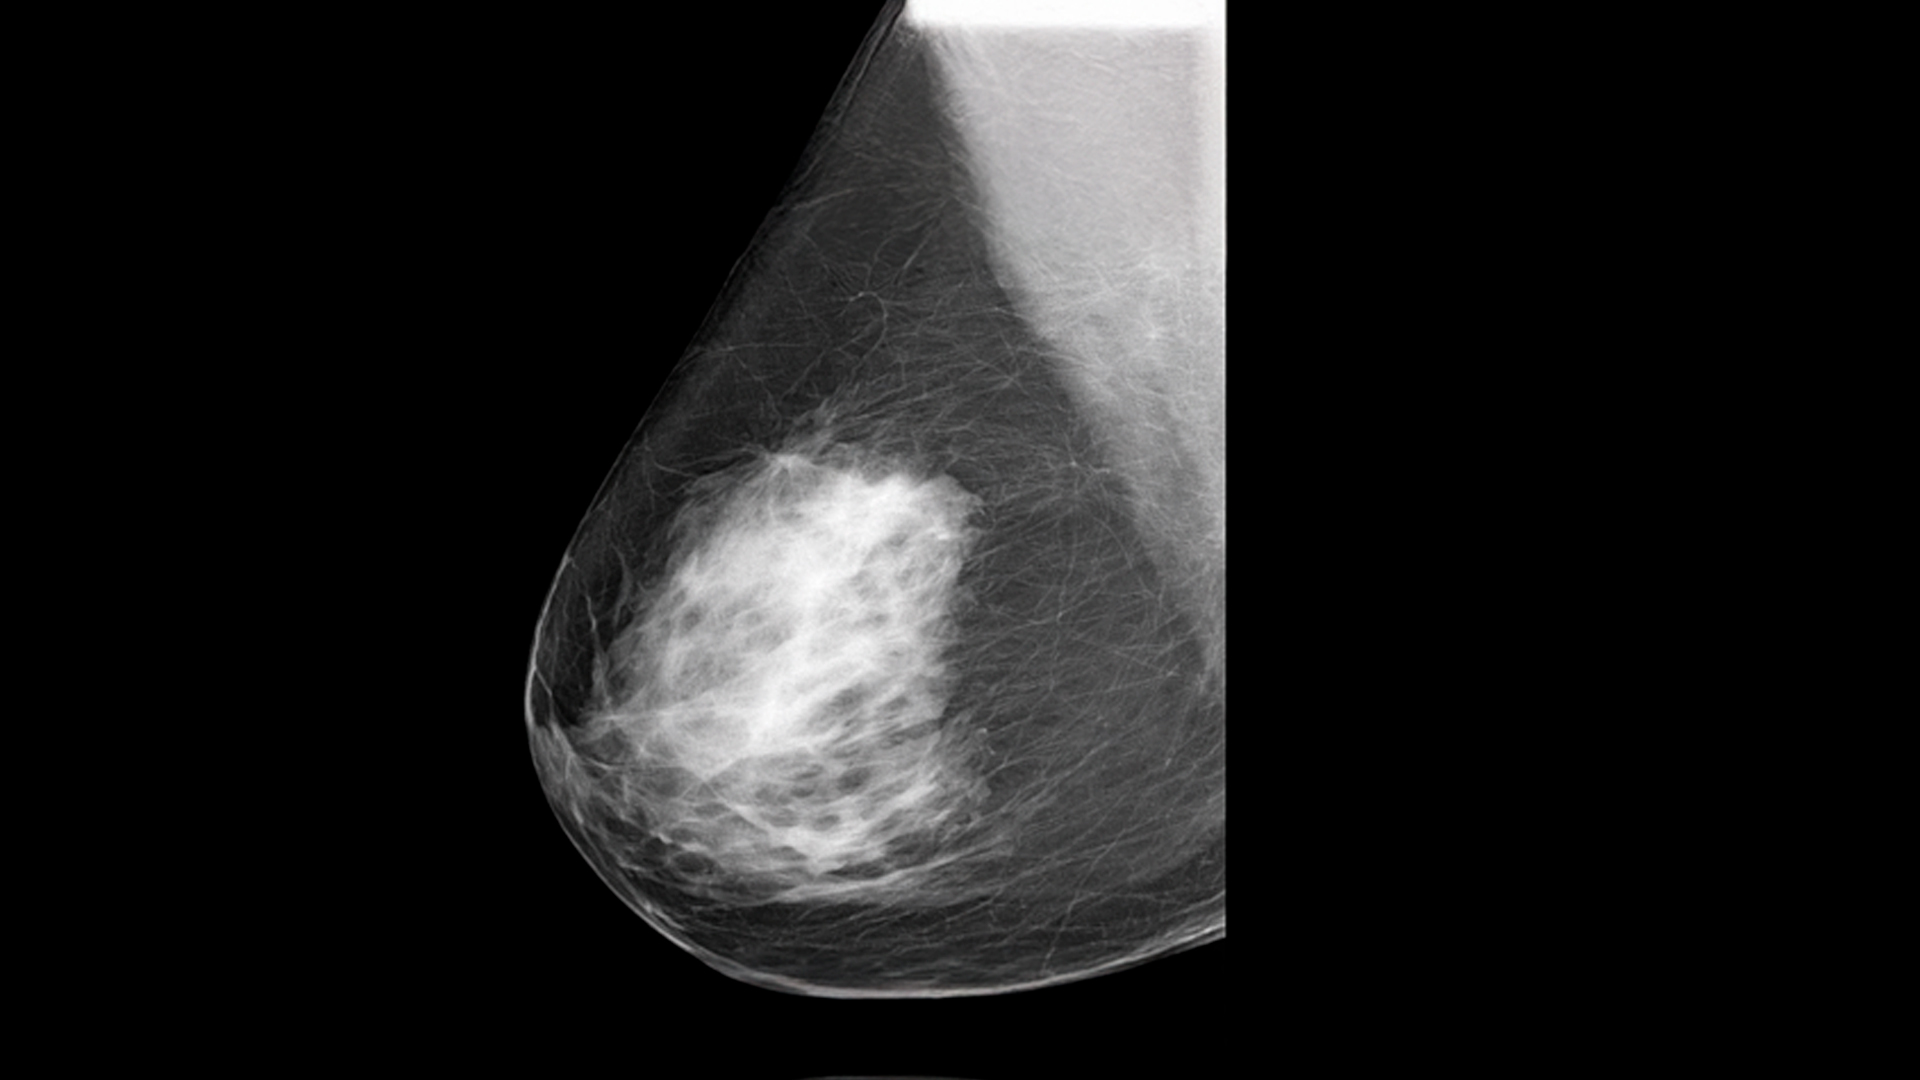

Síntomas de cáncer de mama que todas las mujeres deben conocer

👉👉 Muchas mujeres creen que el cáncer de mama solo se detecta cuando aparece un pequeño bulto.

1. Bulto o masa en el seno o la axila 🍊

Puede sentirse duro, irregular o diferente al tejido habitual. No todos duelen.